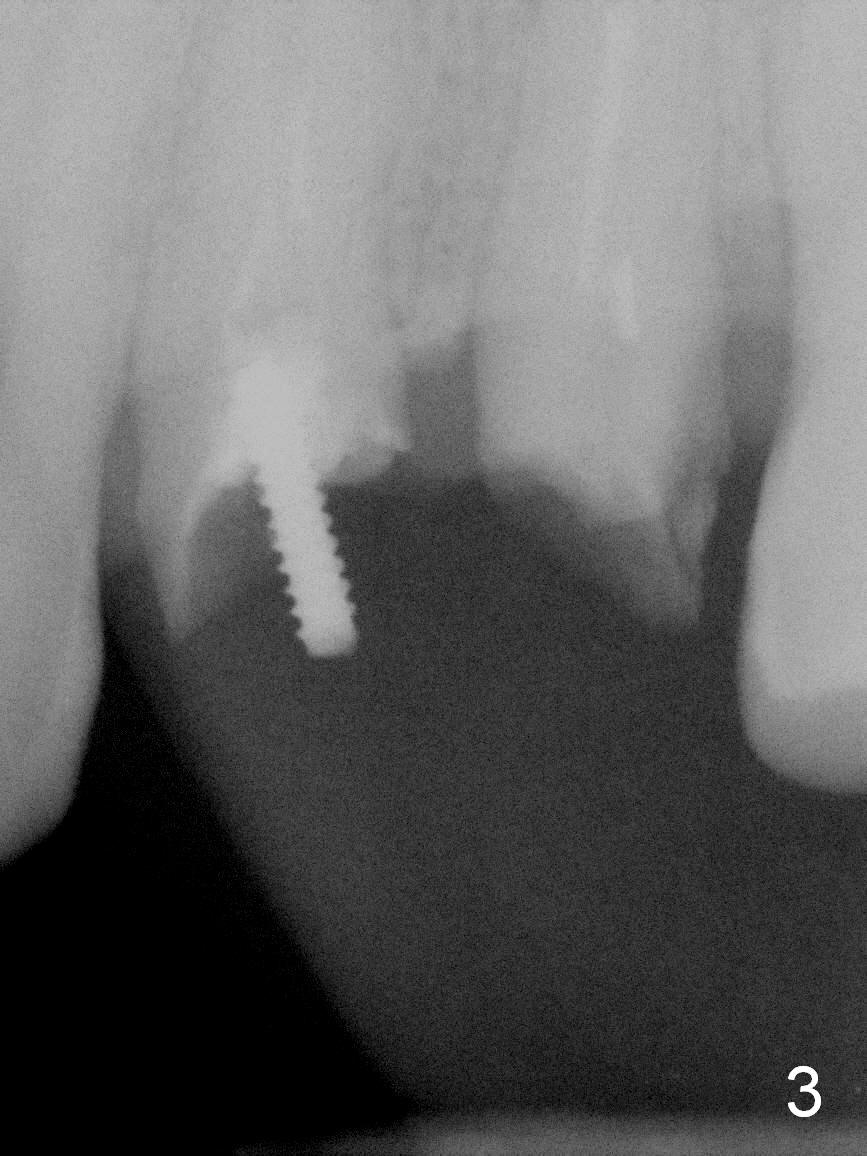

A 45-year-old man presented to our office 8 years ago (Fig.1,2) and got work done somewhere else. He returned yesterday with chief complaint "I might swallow my crowns". Exam shows residual roots at #12,13 (Fig.3,4). The patient has strong jaw bone, suggesting that the bone density is high. Either bone- (Fig.5) or tissue- (Fig.6) level implants will be placed. By time sequence, this case will be assigned to the control group of the antibiotic study. Preop PA does not catch the apices (Fig.3). Take a new one with sensor 1 prior to surgery or panoramus.